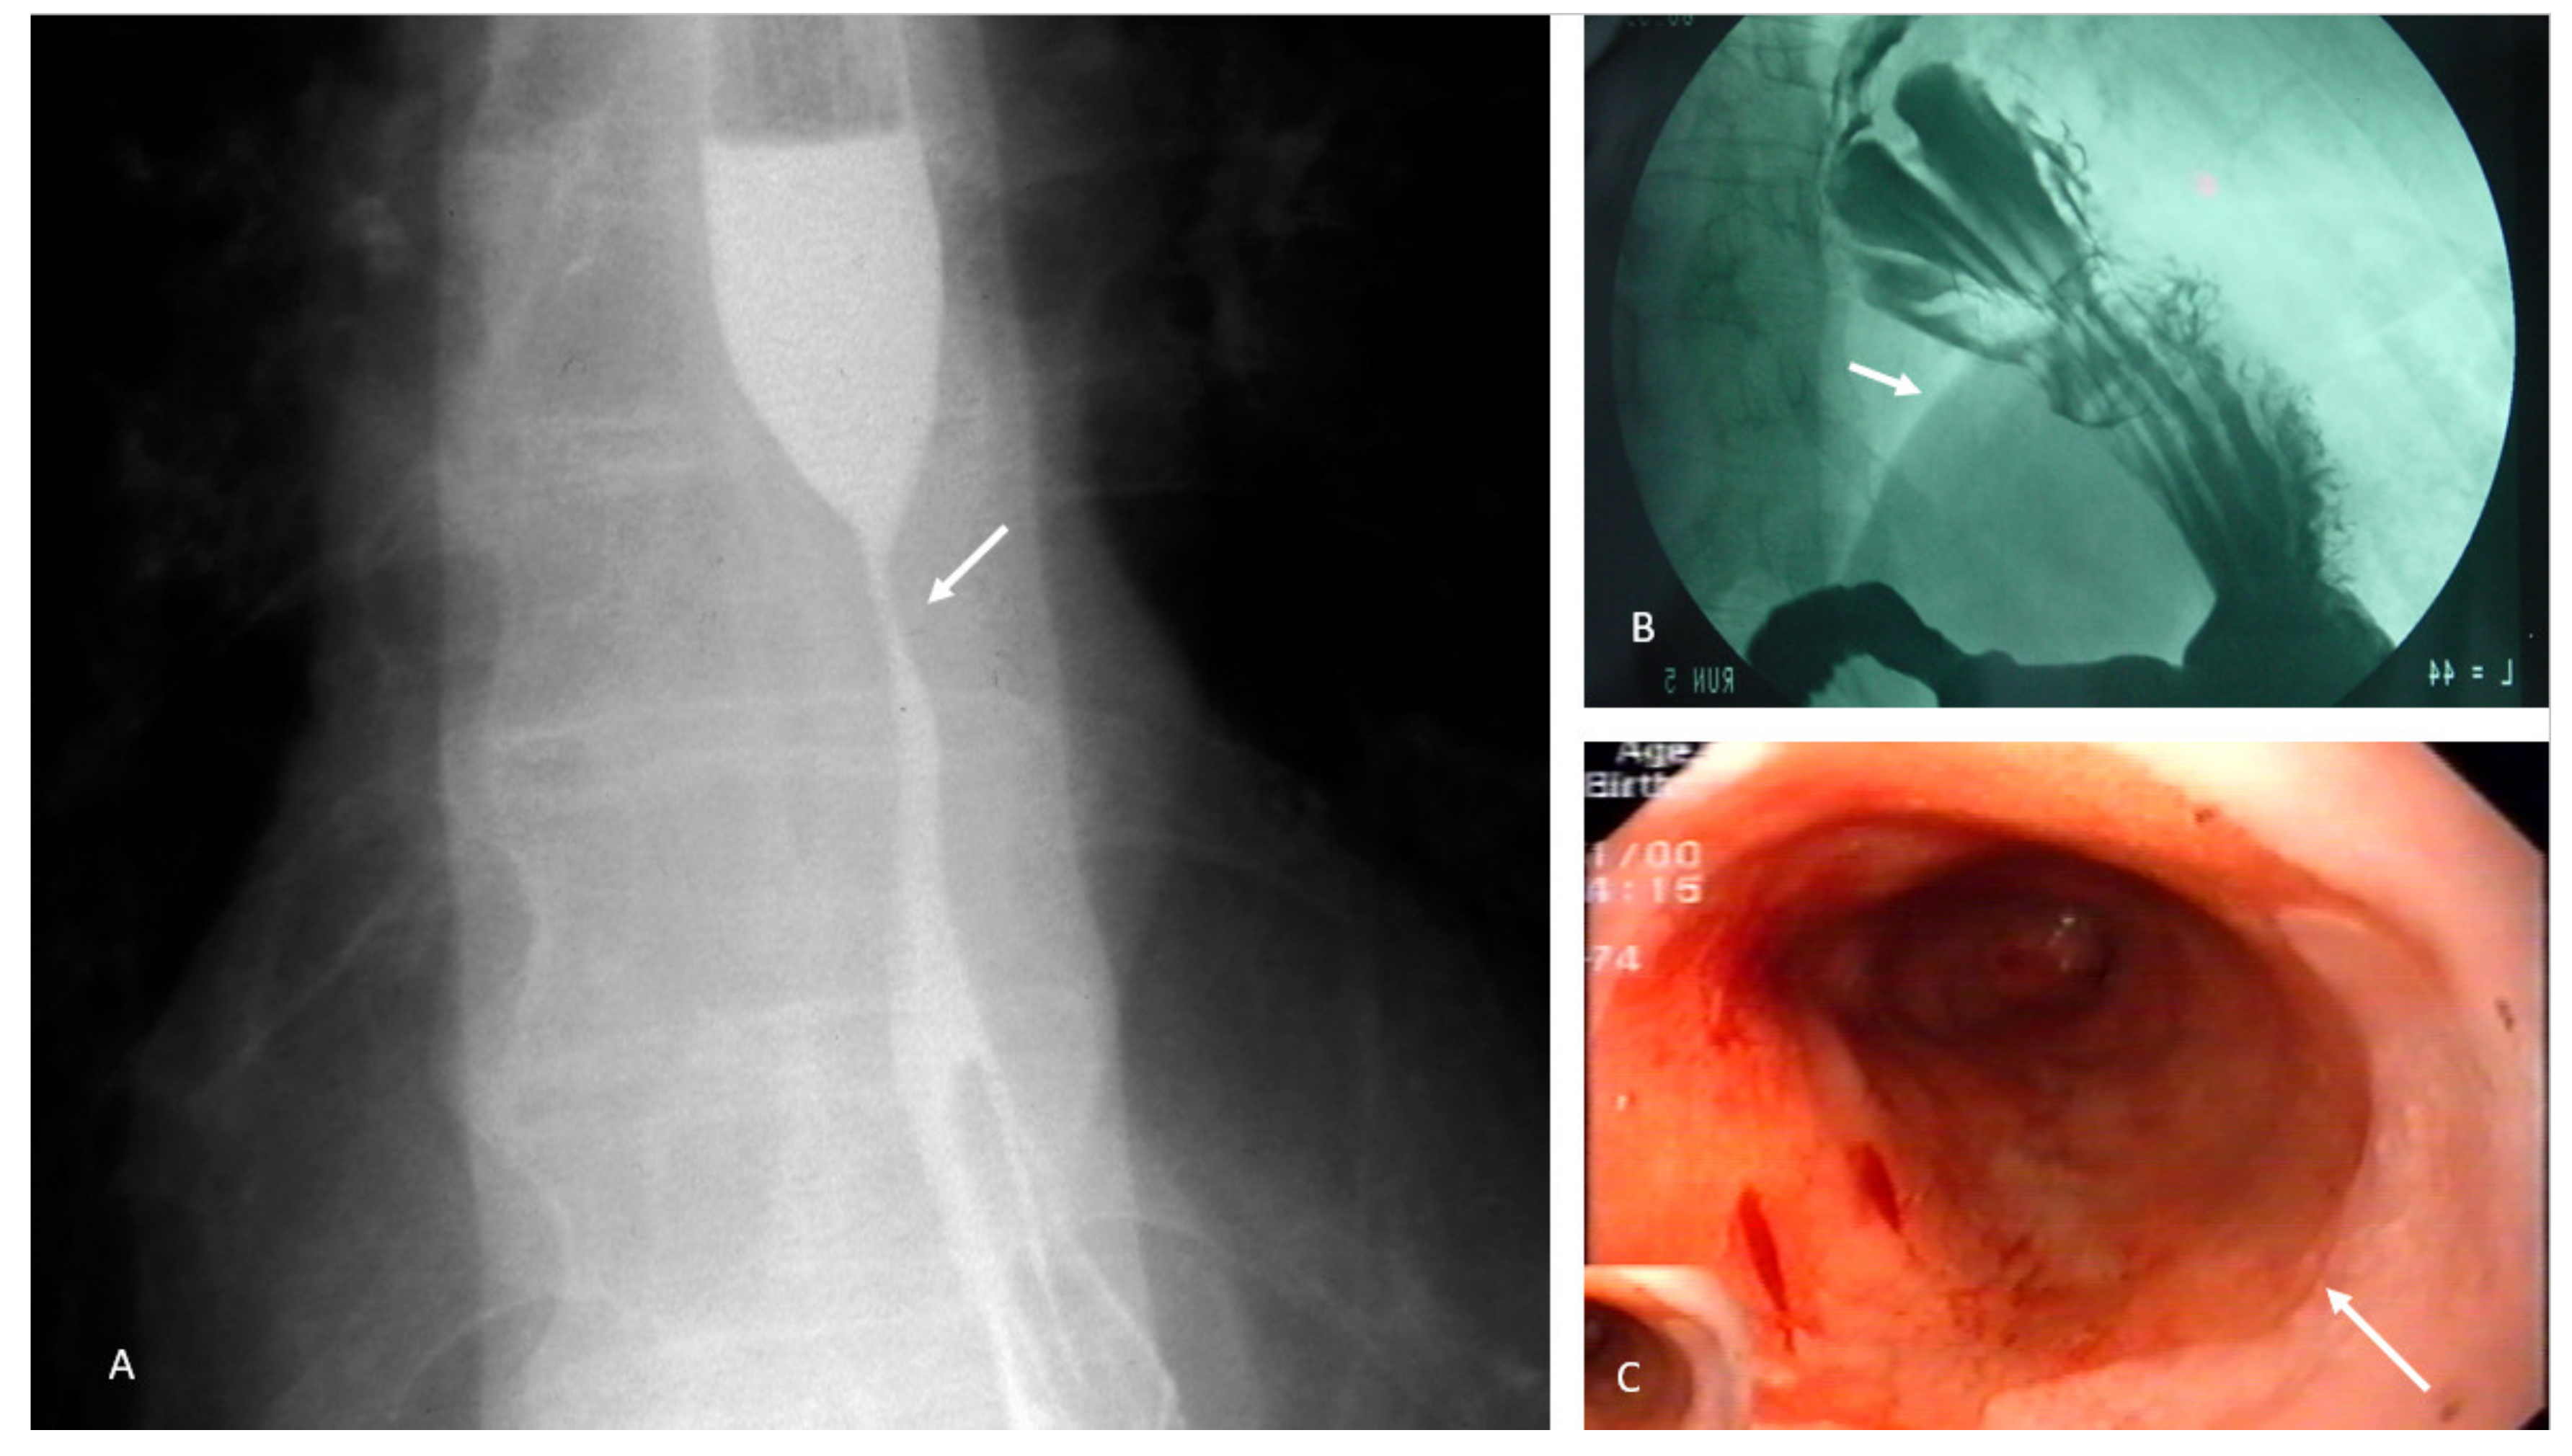

4.2. Achalasia

- Smooth muscle relaxants;

- Botulinum toxin injections to the lower sphincter;

- Pneumatic dilation;

- Heller myotomy;

- Peroral endoscopic myotomy.

4.3. Eosinophilic Esophagitis